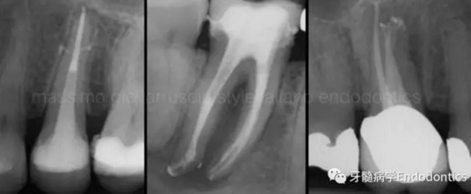

圖1.探查冠方2/3可以獲得有關根管系統(tǒng)解剖形態(tài)的相關信息,獲得根管彎曲和多重彎曲程度,或者是否存在根管彎曲的一些重要反饋。醫(yī)生需要重視五種可能遇到的根管解剖類型(包括融合、彎曲、多重彎曲、分歧、分支)。

當建立直線通路、找到所有的根管口后,重心應轉移到根管預備上。若牙髓存在活力且持續(xù)滲血,應使髓室內充滿粘性螯合劑。在牙髓已壞死的情況下,應使用加熱的5.25%次氯酸鈉溶液沖洗并徹底充滿髓室。探查前,根據術前X線片測量并預彎小的不銹鋼銼,以順應預估的根管長度及彎曲度。使用0.02錐度的10號不銹鋼手用K銼探查根管冠方2/3。